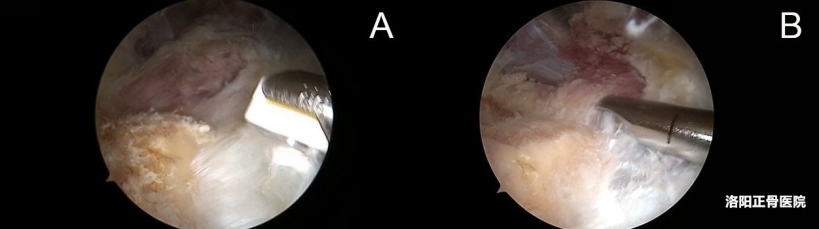

3. 建立双入路:微创通道的精准构建

两个内侧入路位于肱骨内上髁前1cm处并上下各 2-3cm 位置,用11号尖刀做两个 4-5mm 长的小切口,分别作为观察入路和工作入路。从远端切口插入镜鞘和鞘芯,钝性分离皮下组织与深筋膜间隙,确认内上髁位置后插入关节镜;近端切口插入射频设备,射频和镜头在皮下 “会师”,为后续操作建立通道。

操作关键:切口长度仅需容纳镜鞘和器械即可,钝性分离皮下避免损伤浅表神经血管,确保通道安全。

图注:两个入路位于内上髁前方1cm并上下各2-3cm位置,尺神经标记于内上髁后方,术中标记呈笑脸状

图注:近端入路观察,远端入路操作,进一步清理深筋膜和皮肤之间的组织,显露二头肌肌腱向前臂内侧延伸的筋膜和与其垂直相交的前臂屈肌群筋膜。